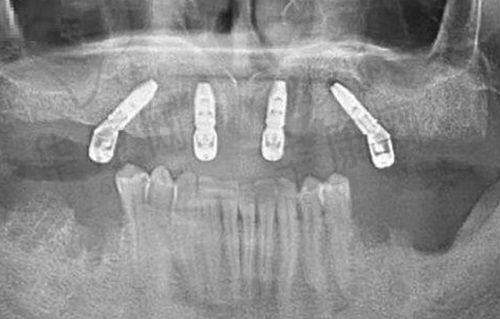

西双版纳竹子口腔医院提供牙科、口腔外科、口腔美容等多方位的口腔医疗服务,涵盖牙齿疾病、口腔黏膜疾病、口腔颌面外伤等多个方面。无论是简单的龋齿治疗,还是复杂的种植牙手术,都能在这里找到相应的解决方案。医院引进了高端的数字化诊疗设备,并采用标准化的诊疗流程,确保诊疗过程的精细性和安心性。例如,在种植牙手术中,数字化设备可以帮助医生更正确地规划种植位置和角度,提高手术的成功几率。医院拥有一支经验多的医护团队,所有医生均持有正规的执业资格证书,并在各自的擅长领域拥有丰富的临床经验。他们不仅技术不错,而且态度亲切,能够耐心解答患者的疑问,并提供有效的诊疗建议。